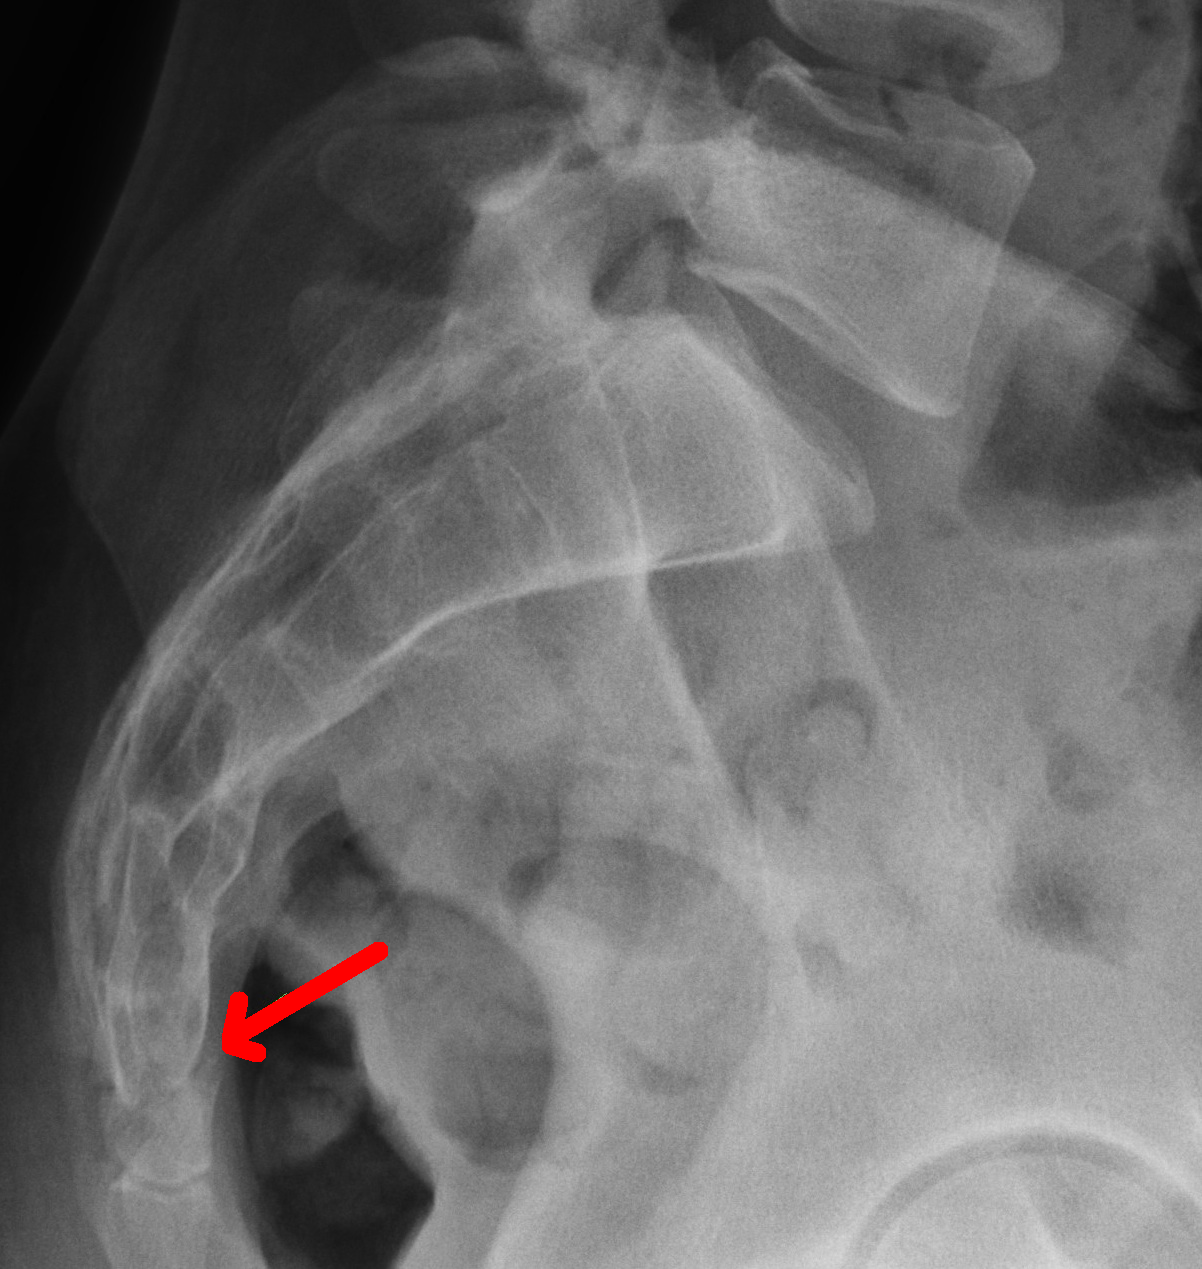

Рентгеновские снимки крестцово-копчикового отдела позвоночника